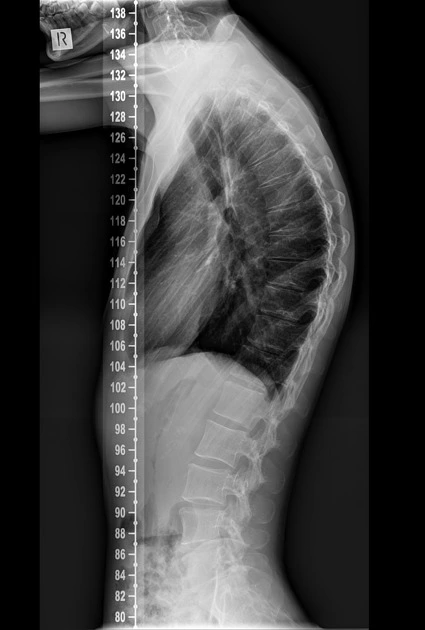

Hyperkyphosis, often referred to as a hunchback posture or an excessive curve in the upper back, is a spinal disorder characterized by an abnormal rounding of the thoracic spine. In a healthy spine, there’s a natural curve in the thoracic region, typically ranging from 20 to 45 degrees. However, in individuals with hyperkyphosis, this curve exceeds 45 degrees, leading to a noticeable hunch in their posture.

Diagnosing hyperkyphosis typically involves a comprehensive physical examination and a review of your medical history. Your chiropractor may assess your spine’s flexibility, strength, and alignment, as well as look for any signs of nerve compression. Imaging studies like X-rays, CT scans, or MRIs may also be ordered to get a detailed view of your spine and assess the severity of the curvature.